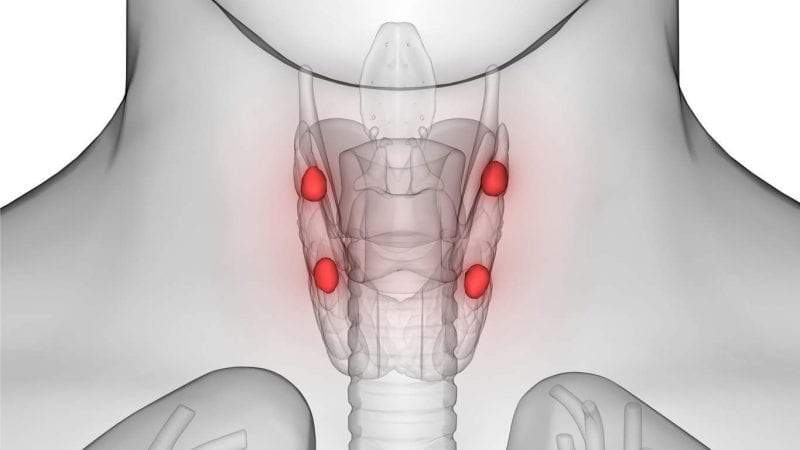

عملية استئصال الغدة جار الدرقية يتم اللجوء إليها في بعض الحالات مثل فرط النشاط والأورام السرطانية وغيرها، والغدة جار الدرقية لها أهمية كبيرة في جسم الإنسان حيث إن لها دور في الحفاظ على المستوى الطبيعي للكالسيوم في الجسم، ولكن في بعض الأحوال قد يضطر الطبيب لعمل إجراء استئصال هذه الغدد الصغيرة التي توجد خلف الغدة الدرقية، والغدد جار الدرقية هي 4 غدد بحجم حبة الأرز موجودة في الجزء الأمامي السفلي من الرقبة، تعالوا معي لكي نتحدث في هذا الموضوع عن عملية استئصال هذه الغدد وأسباب ذلك.

- فرط نشاط الغدة جار الدرقية أو تضخمها، حيث إنه في بعض الأحيان تتضخم إحدى الغدد جار الدرقية مما يؤدي إلى زيادة إفراز هرمون الباراثورمون وبالتالي تحدث بعض المشاكل في مستويات الكالسيوم في الجسم، لذا يكون الحل الأمثل في هذه الحالات هو استئصال إحدى الغدد جار الدرقية.

- أورام الغدة جار الدرقية، حيث إنه قد تحدث بعض الأورام في الغدد جار الدرقية سواء كانت أوراما حميدة أو خبيثة، وبالتالي يضطرب إفراز الهرمون مما يؤدي إلى مشاكل في مستويات الكالسيوم أيضا وبالتالي قد يتم اللجوء إلى عملية استئصال الغدة جار الدرقية في هذه الحالات.